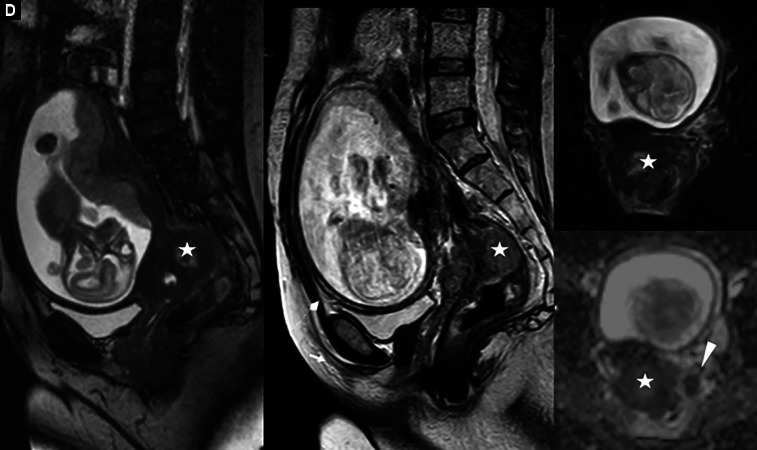

Case description: A 45-year-old female primigravid, pregnant woman, in the 20th week of gestation presented with complaints of multiple episodes of bloody diarrhea and tenesmus for the past 3 weeks. This was accompanied by poor appetite and weight loss (15 kg) since the onset of pregnancy. The patient also complained of lower back and abdominal pain. Investigations confirmed an obstructing rectosigmoid mass (15 cm) that could not be passed. The patient's pregnancy was terminated, and chemotherapeutic treatment was initiated.